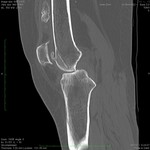

Окончательное мнение - костно-хрящевой экзостоз. Прилагаю РКТ коленного сустава (пациент не тот, что на МРТ)

О! Это понятно: экзостозы (2), остеофиты, очаги окостенения в мягких тканях.

За надколенником по передней поверхности бедренной кости на МРТ и РКТ (наверное не так наглядно) - костно-хрящевой экзостоз.

+ на РКТ проекционно на уровне средней трети диафиза бедренной кости кпереди от нее - фокусы хондроматоза.